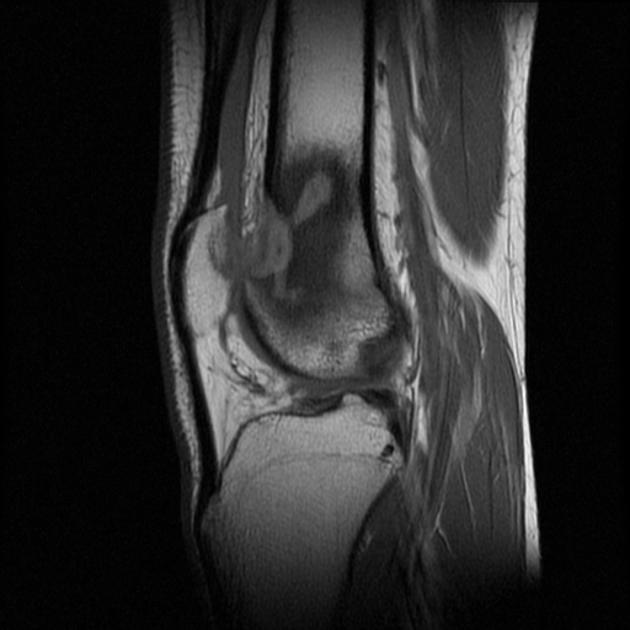

Frond like fatty tissue affecting the joint or bursa

Lipoma Arborescens

5th-7th decades

Bright on T1 and T2 and saturates on fat sat sequences